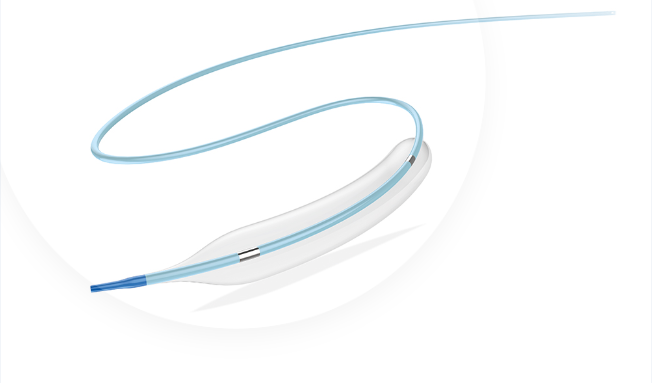

Tadpole™

Coronary Dilation Catheter

Coronary Dilation Catheter

Tadpole™ and Mini Tadpole™ models. Available in Compliant and Semi-Compliant versions.

CORONARY DILATATION CATHETER

Tadpole ™ & MiniTadpole ™

This catheter is a kind of rapid exchange catheter with an integrated shaft system and a balloon near the distal tip. The balloon has two radiopaque markers to aid in positioning the balloon in the stenosis, and is designed to provide an expandable segment of known diameter and length at a specific pressure.

0.017" SOFT TAPERED TIP

SHORT AND ROUND SHOULDER DESIGN

HYDROSURF ™ COATING ON DISTAL SHAFT

PEBAX BALLON MATERIAL

GREAT RE-FOLDING ABILITY

AVAILABLE: COMPLIANT AND SEMI-COMPLIANT

Hydrosurf ™ Coating

Patented hydrophylic coating ondistal shaft provides outstanding deliverability

0.017" Soft Tapered Tip

Enhance the crosability and avoid of "fish mouth" to minimize teh damate to vessel wall

Short and Round Shoulder

Ensure the precise dilatation, and reduce the damage to normal vessel next to the lesion